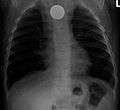

A coin seen on AP CXR in the esophagus

A coin seen on lateral CXR in the esophagus